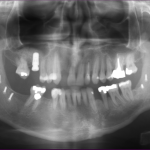

The bone used in a sinus lift may come from your own body (autogenous bone), from a cadaver (allogeneic bone) or from cow bone (xenograft). You will need X-rays taken before your sinus lift so the dentist can study the anatomy of your jaw and sinus. You also may need a special type of computed tomography (CBCT) scan. This scan will allow the dentist to accurately measure the height and width of your existing bone and to evaluate the health of your sinus.